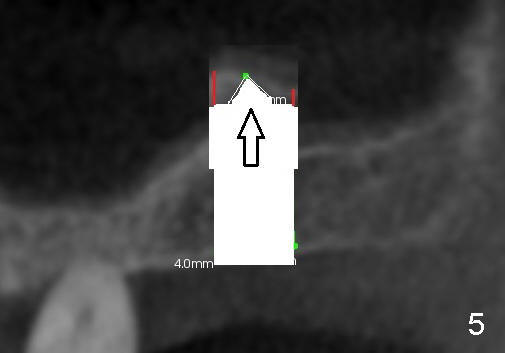

Fig.1 shows the sagittal section of the upper right posterior quadrant (3: #3 palatal root, 2: edentulous area to receive implant; S: sinus). The bone height is 5.8 mm. If the trephine bur with 4 mm outer diameter) does not engage into the bone easily, a 2.0 mm pilot drill is used to create initial osteotomy short of sinus floor (~4 mm deep). Osteotomy is increased by sequentially using 2.5, 3.0, 3.5 and 4.0 mm reamers (Fig.3). Bone shaving is saved. The last 1-2 mm of osteotomy (i.e., sinus floor) is prepared using 4 mm trephine bur (Fig.4 red lines). A flat end osteotome (4 mm in diameter, Bicon comprehensive kit) or tap is used to push the sinus floor upward gently and slowly (Fig.5 arrow). Use a small curet to separate the sinus membrane off the sinus floor lateral to the osteotomy. Put the saved autogenous bone graft back to the osteotomy. Push it upward with Bicon bone condenser. When an implant is placed (Fig.6 pink outline, e.g., 6x11 mm), the top is covered by the vital bone, whereas the side by the harvested bone (*, although the latter loses direct blood supply).